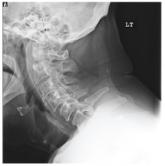

Man with Decreasing Consciousness and Increasing Confusion

- Author:

- Nandan Hichkad, PA-C, MMSc

Publish date: December 1, 2010